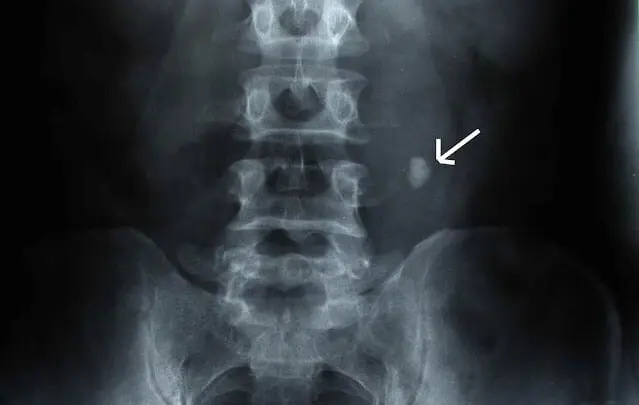

2.泌尿系统结石:肾盂、输尿管、膀胱、尿道任意部位的结石。

X线显示结石(箭头所示)